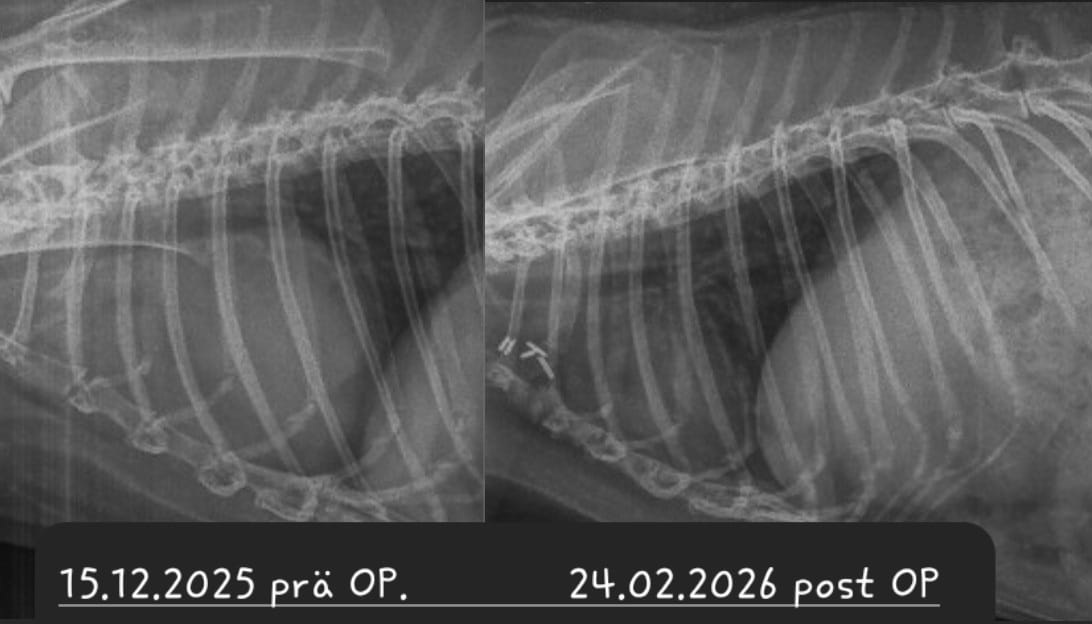

Bei einer Thymom- oder Lymphom-OP handelt sich um einen schwerwiegenden Eingriff, bei dem der Brustkorb des Patienten eröffnet wird und der Tumor möglichst vollständig entfernt werden muss, ohne dabei das benachbarte Herz zu schädigen. Die OP wird nur von wenigen Chirurgen angeboten. Ein Spezialist, der regelmäßig auch Patienten aus Deutschland operiert, ist Dr. Florent Modesto in Brüssel.

Sofern davon auszugehen ist, dass das Kaninchen den Eingriff übersteht und der Tumor sich vollständig entfernen lässt, ist die OP zwar die kostspieligste, aber vermutlich auch die Option mit der besten Prognose

Leider ist trotz allem damit zu rechnen, dass Zellreste des Tumors zurückbleiben und nach einiger Zeit nachwachsen. Je nach Tumor-Art ist dies allerdings mitunter erst nach 3-5 Jahren der Fall - womit das Kaninchen sehr viel Lebenszeit gewonnen hat; hinzu kommt die verbesserte Lebensqualität, nachdem die Masse aus dem Brustkorb entfernt wurde und langfristig auch keine Medikamente gegeben werden müssen.

Nach der chirurgischen Entfernung des Tumors bleibt der Patient stationär am Schmerzmittel-Dauertropf, bis er stabil bei gutem Allgemeinbefinden ist.

Um eine komplikationslose Heilung der Nähte und des Brustbeins zu gewährleisten, muss das Kaninchen in den ersten 4 Wochen nach der OP in einem kleinen Krankenbereich (Zimmerkäfig oder kleines Gehege) untergebracht werden, da es keinesfalls rennen, springen oder übermäßig hoppeln darf.